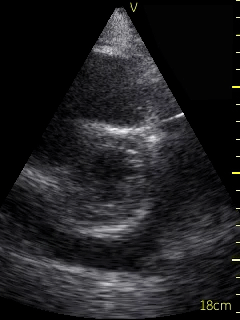

Video 1 (online supplement; Figure 1) demonstrates a parasternal long axis view with the pericardial effusion noted to be posterior to the left ventricle in this view. Video 2 (online supplement; Figure 2) is a short axis view of the heart which is showing that the effusion is surrounding the heart. Video 3 and 4 (online supplements; Figures 3 & 4) demonstrates that the pericardial effusion is present significantly surrounding the apex as well. An echocardiogram confirmed the POCUS findings and cardiology was consulted to conduct a pericardiocentesis, following which the patient’s symptoms resolved. The effusion was thought to be chronic and transudative. In this case, the use of POCUS at the bedside allowed for rapid detection of a large pericardial effusion and subsequent treatment.